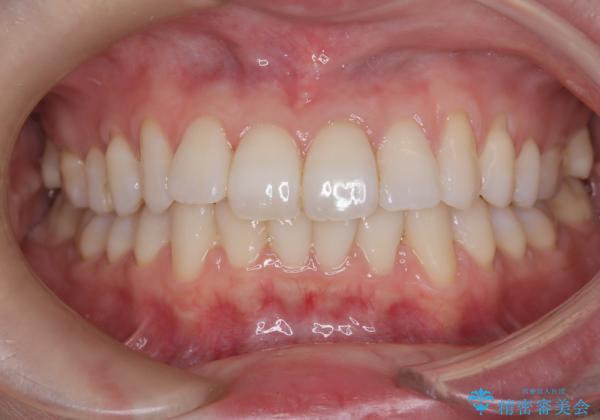

前歯の叢生は解消され、自然で調和の取れた歯並びが得られました。

「歯をほとんど削らずにきれいになった」と、患者様にもご満足いただけました。